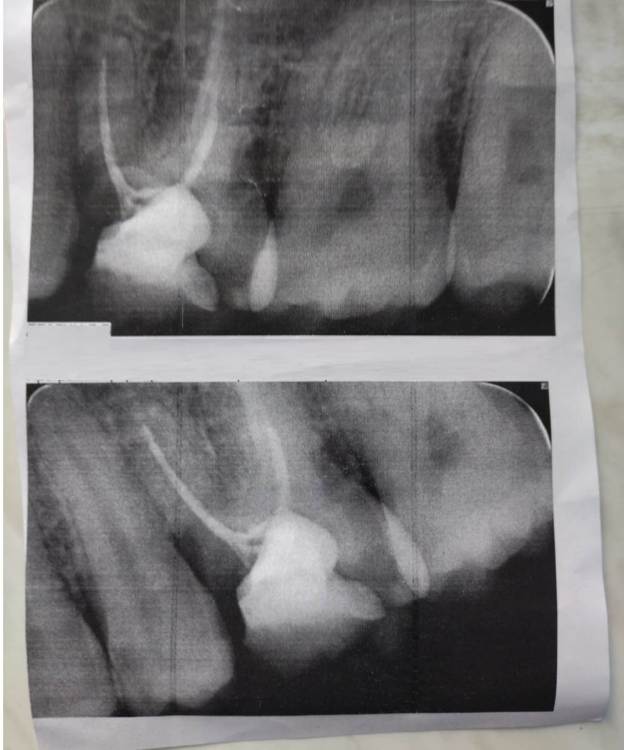

Avrog Опубликовано 26 марта, 2022 Поделиться Опубликовано 26 марта, 2022 Здравствуйте! Имеется определенные проблемы , скорее всего, с десной на данный момент, но непонятны причины и что следует предпринять в данном случае . Пациентке 25 лет. Предыстория такова , что имелись раннее проблемы сперва с 6ой . ,- кариес. Пролечили в 20 лет. Удалили нерв, запечатали - поставили пломбу . Это было сделано в поликлинике, пломба платная. Далее в 22 года начались проблемы с 7 ым зубом , кариес . В процессе восполилась десна , появился "карман" -рядом с семёркой, изначально болел непосредственно зуб ., вероятно это спровоцировало восполнение десны. В частной клинике повторили процедуру с 7 ой , поставили большую пломбу., Но нерв оставили. Через год у 7ки откололось часть пломбы, в клинике переделывали процедуру , ставили временную пломбу , удалили нерв , установили большую пломбу . По итогу имеем два мертвых зуба. Зубы не болят . Около двух недель назад восполилась десна, уже ближе к 6 ее. Болело не сильно, ноещее ощущение. Восполнение не сильное , едва заметное на внешний вид. Перед посещением врача , наконуне при чистке зубов - закровоточило из десны . Небольшое количество крови . Боль уменьшилась . При осмотре у врача в платной поликлиники ( первая ближайшая в день обращения) было сказано , что кармана большого нет, с выделением крови и небольшого количества гноя ( со слов доктора ) почистили место восполнения под. десной. Рекомендовали заменить обе пломбы , якобы часть пломбы задевало каким то образом десну , так как пломба могла осесть . Выписали Метрогил Дентал , чтобы постараться снять восполнение. В течении недели применяли гель . Записались на прием в клинику , где лечили изначально 7 ку . При беголом осмотре рекомендовали поставить коронки на мертвые зубы . Не особо хотели менять повторно пломбы на мертвых зубах. Записали на прием к ортодонту При повторном осмотре ортодонта пояснили, что проблем с зубами нет , боли не обнаружили . Рекомендовали обратиться к парадонтологу . Боль появлялась только при введении инструмента под десну, это скорее естественная боль. На данный момент десна не болит, восполнения не видно . Продолжают применение геля ватной палочкой под десну . При процедуре неприятный запах отсутствует , хотя изначально такой присутствовал . Прошу проконсультировать и посоветовать стамоталогический кабинет в Санкт-Петербурге. Сетевым клиникам не доверяю . Очень хочется найти личного стамотолога желательно со своим стам. кабинетом ., Который трудится на себя и не будет навязывать ненужных процедур и услуг. Или посоветуйте надёжного врача, с приемлемым ценам в клинике. Заранее благодарю ! Ссылка на комментарий